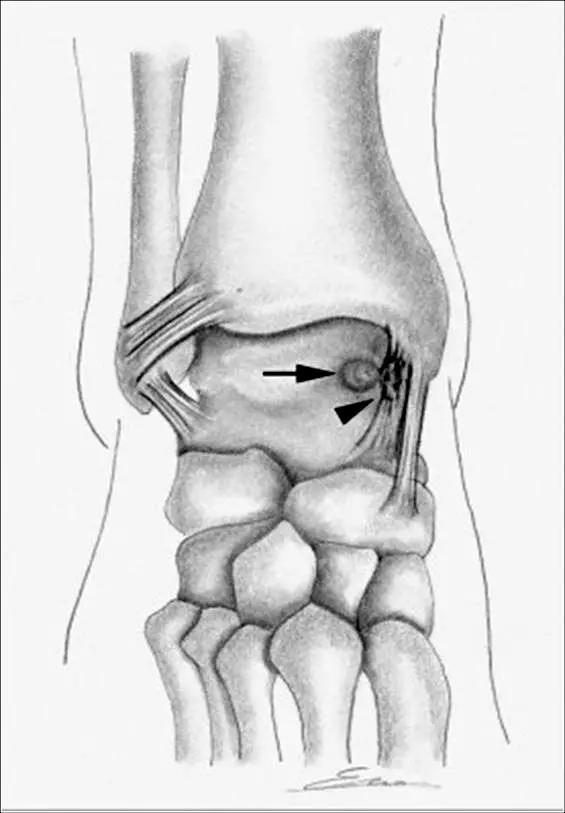

轴位示意图示后内侧撞击综合征:M:内踝;L:外踝;TP:胫后肌腱;FDL:趾长屈肌腱;Talus:距骨。短箭:距骨胫骨间肌腱深层纤维;箭头:距骨胫骨间肌腱后部纤维。

X线平片示胫骨后部骨赘形成,MR质子像黑箭示胫骨内后侧骨赘形成,白箭示内后侧软组织增厚, 白箭头:胫后肌腱;黑箭头:趾长屈肌腱